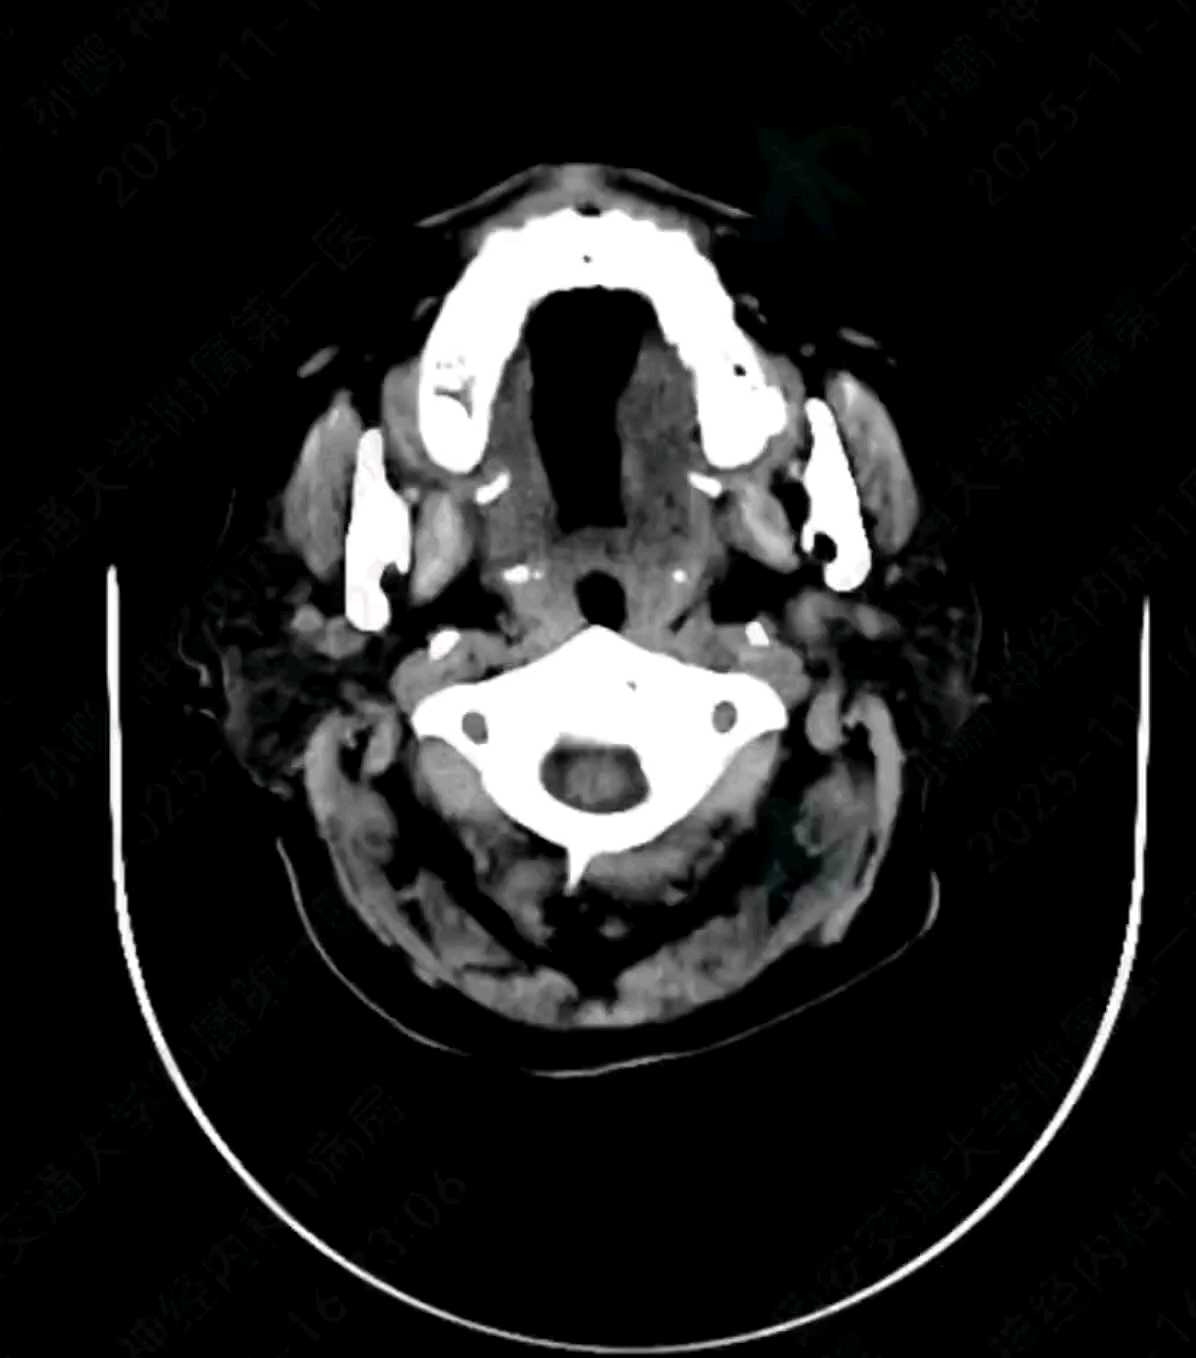

术后24小时复查CT